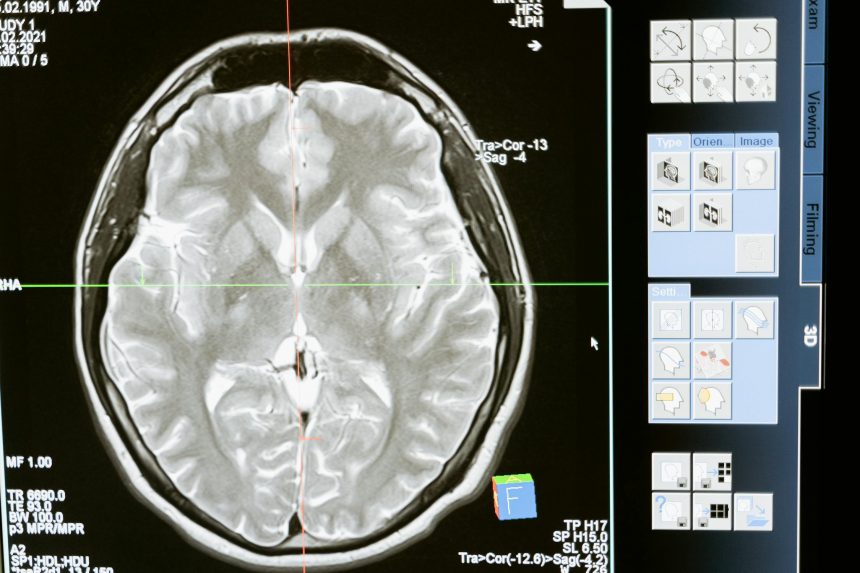

Результаты исследования основаны на данных высокоточной магнитно-резонансной томографии с разрешением 7 тесла, полученных у 60 добровольцев в возрасте от 21 до 80 лет. Анализ показал, что, хотя глубокие слои коры истончаются, средние и верхние нередко демонстрируют устойчивость или утолщение. Эти изменения связаны с активным использованием сенсорных функций и сохранением их значимости на протяжении всей жизни.

Особое внимание ученые уделили первичной соматосенсорной коре — области в верхней части головы, обрабатывающей прикосновения и сигналы от кожи. Эта зона играет ключевую роль в ощущении собственного тела и выполнении привычных действий, таких как удерживание предметов или использование инструментов.

Выяснилось, что верхние слои этой области могут укрепляться с возрастом. Исследователи связывают этот эффект с постоянным вовлечением сенсорных каналов в повседневную активность. При этом нижние слои, регулирующие силу тактильных сигналов в зависимости от контекста, наоборот, становятся тоньше.